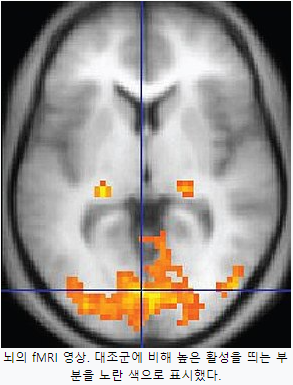

2. fMRI (Functional Magnetic Resonace Imaging) - 기능적 자기공명영상

fMRI는 혈류와 관련된 변화를 감지하여 뇌 활동을 측정하는 기술이다. 뇌의 어떤 부위가 사용될 때 그 영역으로 가는 혈류의 양도 따라서 증가한다는 사실을 이용하여 어떤 부위의 신경이 활성화되었는 측정하는 기술이다.

활성화된 신경세포 주위의 모세혈관에서 산소를 운반하는 헤모글로빈 중에서 산소와 결합된 산화헤모글로빈의 농도는 증가하고, 산소가 분리된 환원헤모글로빈의 농도는 감소한다. 그런데 산화 헤모글로빈은 자성을 띄지 않지만 환원 헤모글로빈은 자성읠 띌 수 있어서 그 주변에 있는 수소원자핵의 자기장 내 반응성에 영향을 미치게 된다. (MRI의 원리가 수소원자핵의 자기장 반응을 보는것) 이에 따라 자기 공명촬영 시 T2신호를 감소시키게 되는데, 앞서 설명한 바와 같이 신경활성이 일어나는 부위에 환원헤모글로빈의 농도가 감소하므로 T2신호는 반대로 증가된다. 따라서 T2신호를 연속적으로 측정하면서, 자기공명 신호의 증가가 일어나는 부위를 찾아내면 곧 활성화된 뇌부위로 추정할 수 있다.